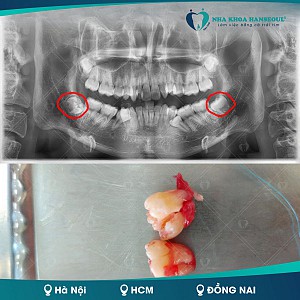

Theo quan niệm thường thấy ở bệnh nhân đó là răng khôn mọc thẳng dễ nhổ và sẽ mất ít thời gian hơn, điều này chỉ đúng một phần. Đánh giá mức độ khó của răng khôn, ngoài hướng mọc ra còn phụ thuộc vào các yếu tố: chiều cao của hàm dưới, góc nghiêng so với răng số 7, hình thể chân răng, hướng thoát của răng, độ tuổi, các cấu trúc giải phẫu liên quan…

Vì vậy, việc thăm khám cũng như chụp phim là vô cùng quan trọng để có cái nhìn ban đầu về răng khôn cũng như mức độ khó của nó.

Bước 2: Chụp phim X-quang 2 chiều hay 3 chiều. Chỉ định chụp phim 3 chiều trong nhổ răng khôn để đánh giá chi tiết mối liên quan của răng khôn với các cấu trúc giải phẫu cũng như đánh giá tốt hơn hình thể chân răng, loại phim này đang dần trở nên thông dụng khi bắt đầu bất kì một tiểu phẫu nhổ răng khôn nào.

Bước 5: Sát khuẩn vùng nhổ, gây tê, nhổ răng và hoàn tất quá trình nhổ răng.

Sau khi bác sĩ nhổ răng sẽ vệ sinh huyệt ổ răng sau nhổ và đánh giá thêm, có thể sẽ khâu cầm máu. Bệnh nhân sẽ được yêu cầu cắn gạc trong 1 tiếng để hạn chế chảy máu và được hướng dẫn chăm sóc sau nhổ răng và hẹn lịch tái khám, cắt chỉ sau 3 đến 7 ngày.